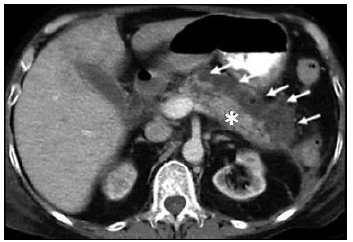

Observe atentamente a seguinte TC abdominal com contraste VOVO e IVIV:

É correto afirmar que a imagem anterior trata-se